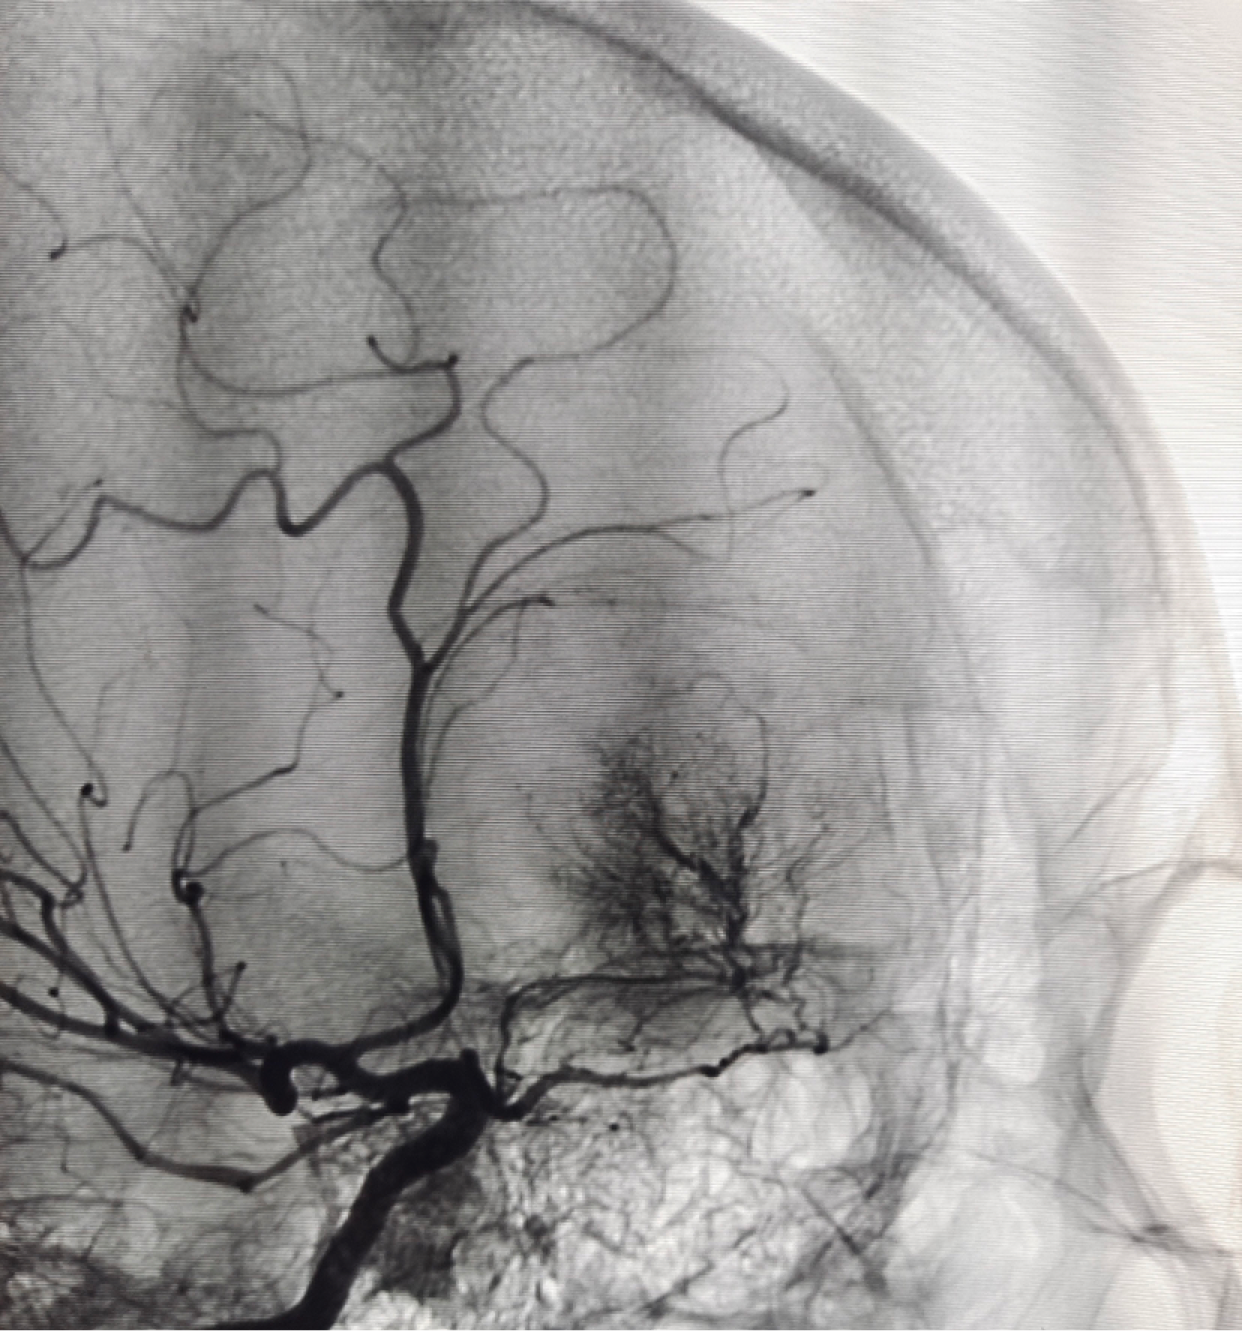

DSA(颈内造影)

DSA(颈外造影)